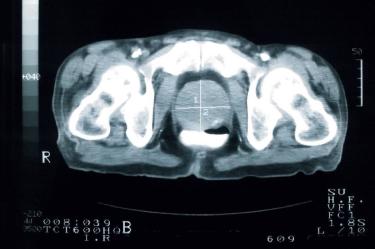

Los cánceres de próstata experimentarán un fuerte aumento en los próximos años en todo el mundo, especialmente en los países menos ricos, a causa del envejecimiento progresivo de la población mundial, según un estudio publicado en la revista The Lancet.

El cáncer de próstata, el más habitual entre los hombres, representa el 15 por ciento del total de cánceres masculinos.

En la mayoría de casos se manifiesta después de los 50 años, y su frecuencia aumenta considerablemente a medida que se avanza en edad más allá de este umbral.